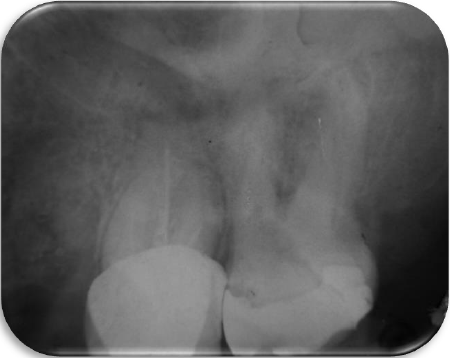

Paciente femenino de 51 años de edad, acude a la clínica de odontología de la Escuela Nacional de Estudios Superiores, Unidad León, UNAM; quien refiere padecer diabetes tipo II controlada farmacológicamente. Es referida a la clínica de profundización de endodoncia y periodoncia donde se realizó examen clínico y radiográfico del diente 17, observándose una restauración con resina mal ajustada y caries (Figura 1).